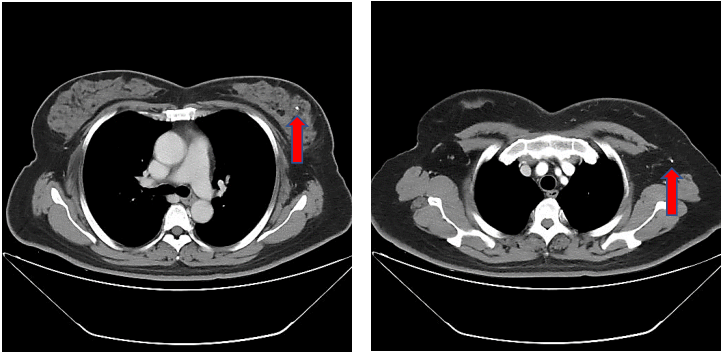

胸部CT平扫提示两肺部纹理清晰,未见确切异常密度影。纵隔内未见确切淋巴结肿大。双侧胸膜未见明显增厚,双侧胸腔未见积液。左乳明显增大,腺体弥漫性致密,左腋下见多发肿大淋巴结影,短径约1.3cm(图3)。

图3.胸部CT平扫

新辅助治疗6周期后再次CT评估,提示两肺未见明显异常密度影。纵隔内未见确切肿大淋巴结。双乳腺体致密,左乳局部可见点状高密度影,未见确切异常强化灶;双侧腋窝未见明显肿大淋巴结(图9)。

图9.新辅助治疗6周期后胸部CT平扫(箭头处提示金属clip位置)